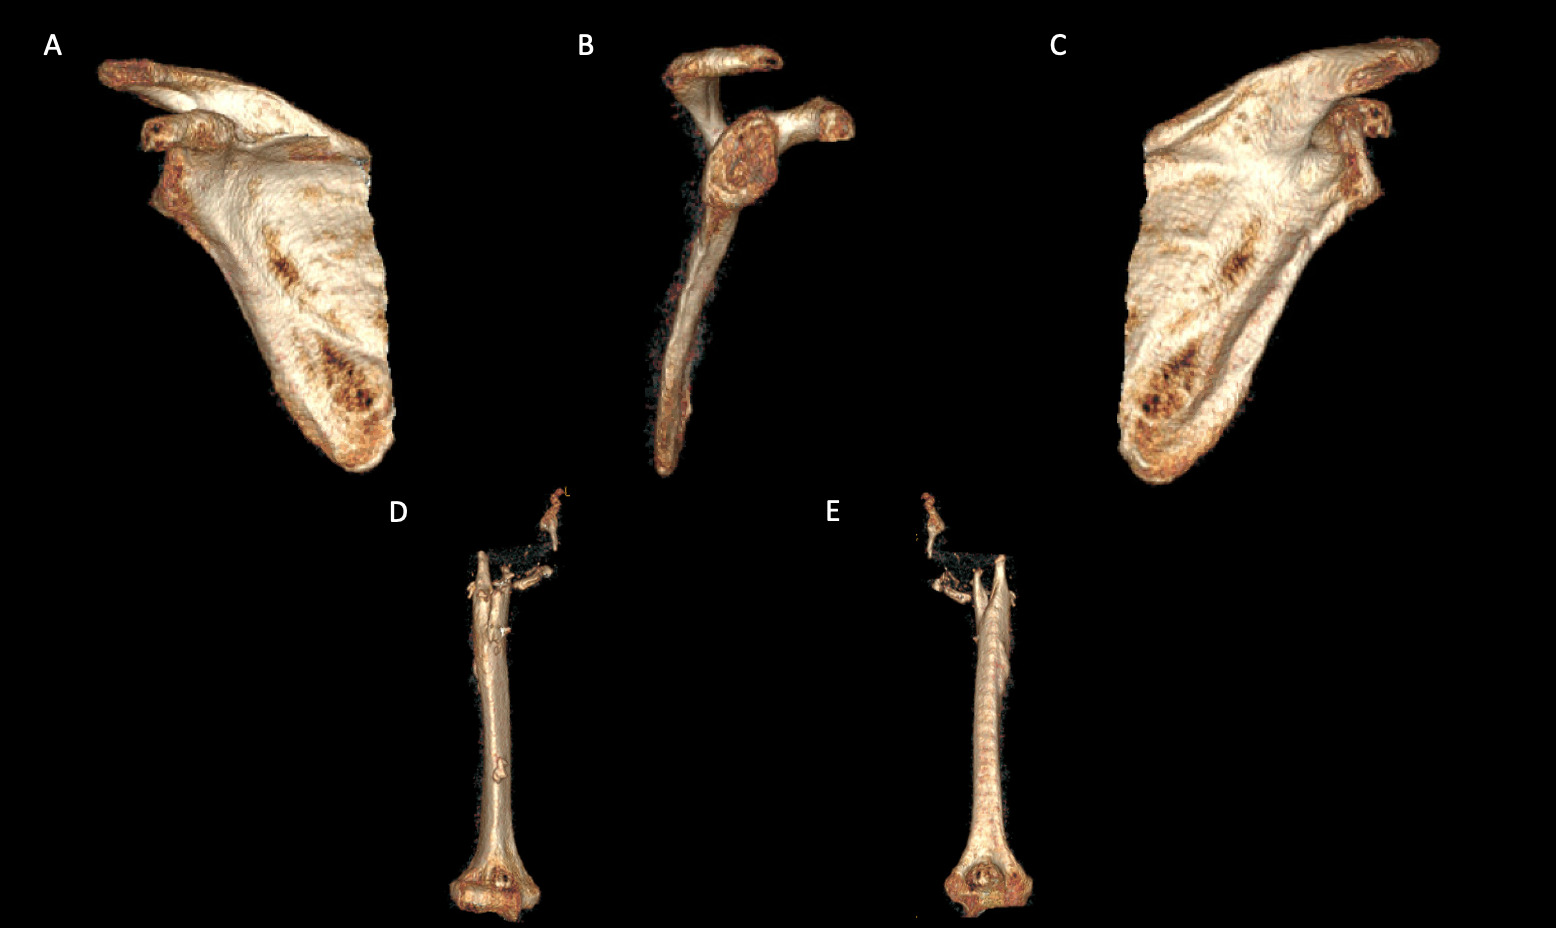

A 69-year-old woman presented after resection arthroplasty of her right shoulder hemiarthroplasty and completion of antibiotic treatment for culture negative PJI for evaluation of reconstructive options. She had a history of a displaced two-part right proximal humeral fracture which was repaired with an intramedullary nail. Post operatively, she had persistent pain and CT scan of the shoulder showed two screws in the humeral head that extended through the cortex and into the glenohumeral joint. The screws were removed and replaced with smaller screws. Subsequently, she had non-union of the fracture in the setting of deltoid weakness and was revised to a right hemiarthroplasty (Figures 1-3). Post operatively, she had persistent pain refractory to physical therapy and diminished function that was impacting her quality of life. She sought subsequent care, and there was concern for arthroplasty failure secondary to a septic versus aseptic condition and the decision to proceed with resection arthroplasty was made. During resection arthroplasty, a significant amount of fluid was expressed from the joint space. The combination of the clinical picture of progressive and persistent pain and the gross expression of fluid were concerning for PJI and the decision to treat was made. It was felt that the extent of humeral bone loss did not allow for a stable cement spacer, so none was placed. Intraoperative joint fluid cultures, anaerobic, and fungal cultures were all negative for growth. Cultures were held for 21 days to rule out C. Acnes infection. Considering the plan for future reimplantation, infectious disease consultation recommended a 6-week course of vancomycin but after 2 days the patient had a transfusion reaction and was switched to daptomycin. She was left with markedly limited active motion associated with severe pain. After completion of the antibiotic course, the patient elected to proceed with revision surgery. This patient had a flattened and distorted glenoid and atrophied rotator cuff musculature demonstrated prior to resection arthroplasty on CT (Figure 4). This patient’s prior hemiarthroplasty had been a tantalum coated, cemented humeral stem with associated marked thinning of the humeral cortex even prior to resection arthroplasty, and this resulted in a large amount of proximal humeral bone loss during the resection (Figure 5). The patient was severely debilitated by the right shoulder and wanted to proceed with reconstruction. Because of the combination of glenoid and humeral bone loss and the lack of rotator cuff attachments, a custom constrained prosthesis design process was initiated, and the implant was available 16 months after the resection arthroplasty. Preoperative 3 phase SPECT (Single Photon Emission Computed Tomography) three phase bone scan, upper extremity CT, and blood work (WBC 5.4, ESR 9, CRP 0.8) showed no suggestion of active infection.

A 62-year-old woman presented for evaluation of her reconstructive options after resection arthroplasty of a right rTSA and completion of antibiotic treatment for culture negative PJI. Her rTSA had been an Encore prosthesis placed due to rotator cuff arthropathy (Figures 6). Post-operatively she had persistent pain, stiffness, and tenderness to palpation that was treated with physical therapy, a steroid injection, and manipulation under anesthesia. An infectious work up due to the chronic and persistent nature of the pain showed WBC 7.4, ESR 53, CRP 1.2. Patient denied further work up with a tagged white cell scan and preferred continued clinical monitoring to observe pattern of symptoms. Eleven months later, she endorsed persistent pain. Repeat infectious work up showed WBC 4.5, ESR 13, and CRP 1.1. Despite the normal inflammatory markers, a 10-day trial of Augmentin was initiated and failed to change her symptoms. The decision to proceed with 1 vs 2 stage reconstruction was made. During resection arthroplasty, a substantial amount of fluid was expressed from the joint capsule concerning for PJI. A cement spacer was placed, and the patient was treated with 6 weeks of vancomycin and cefepime (Figure 7). There was proximal humeral bone loss as the result of resection arthroplasty due to the humeral stem. The glenoid component was loose and associated with glenoid bone loss, further complicated by the need for removal of a broken central screw (Figure 8).

Intra-operative frozen sections, tissue cultures, and gram stain showed no signs of infection. Following treatment, inflammatory markers remained normal (WBC 5.5, ESR 22, CRP 0.9), and aspiration of the shoulder showed no organisms on gram stain and no growth on aerobic, anaerobic, fungal, and acid-fast bacilli cultures. Cultures were held for 21 days to rule out C. Acnes infection. She was left with profoundly limited active motion and severe pain and the patient elected to proceed with revision surgery. Because of the combination of severe glenoid and humeral bone loss and the lack of rotator cuff attachments necessitating a design with additional constraint, the decision to proceed with custom prosthesis design was made 9 weeks after resection arthroplasty.